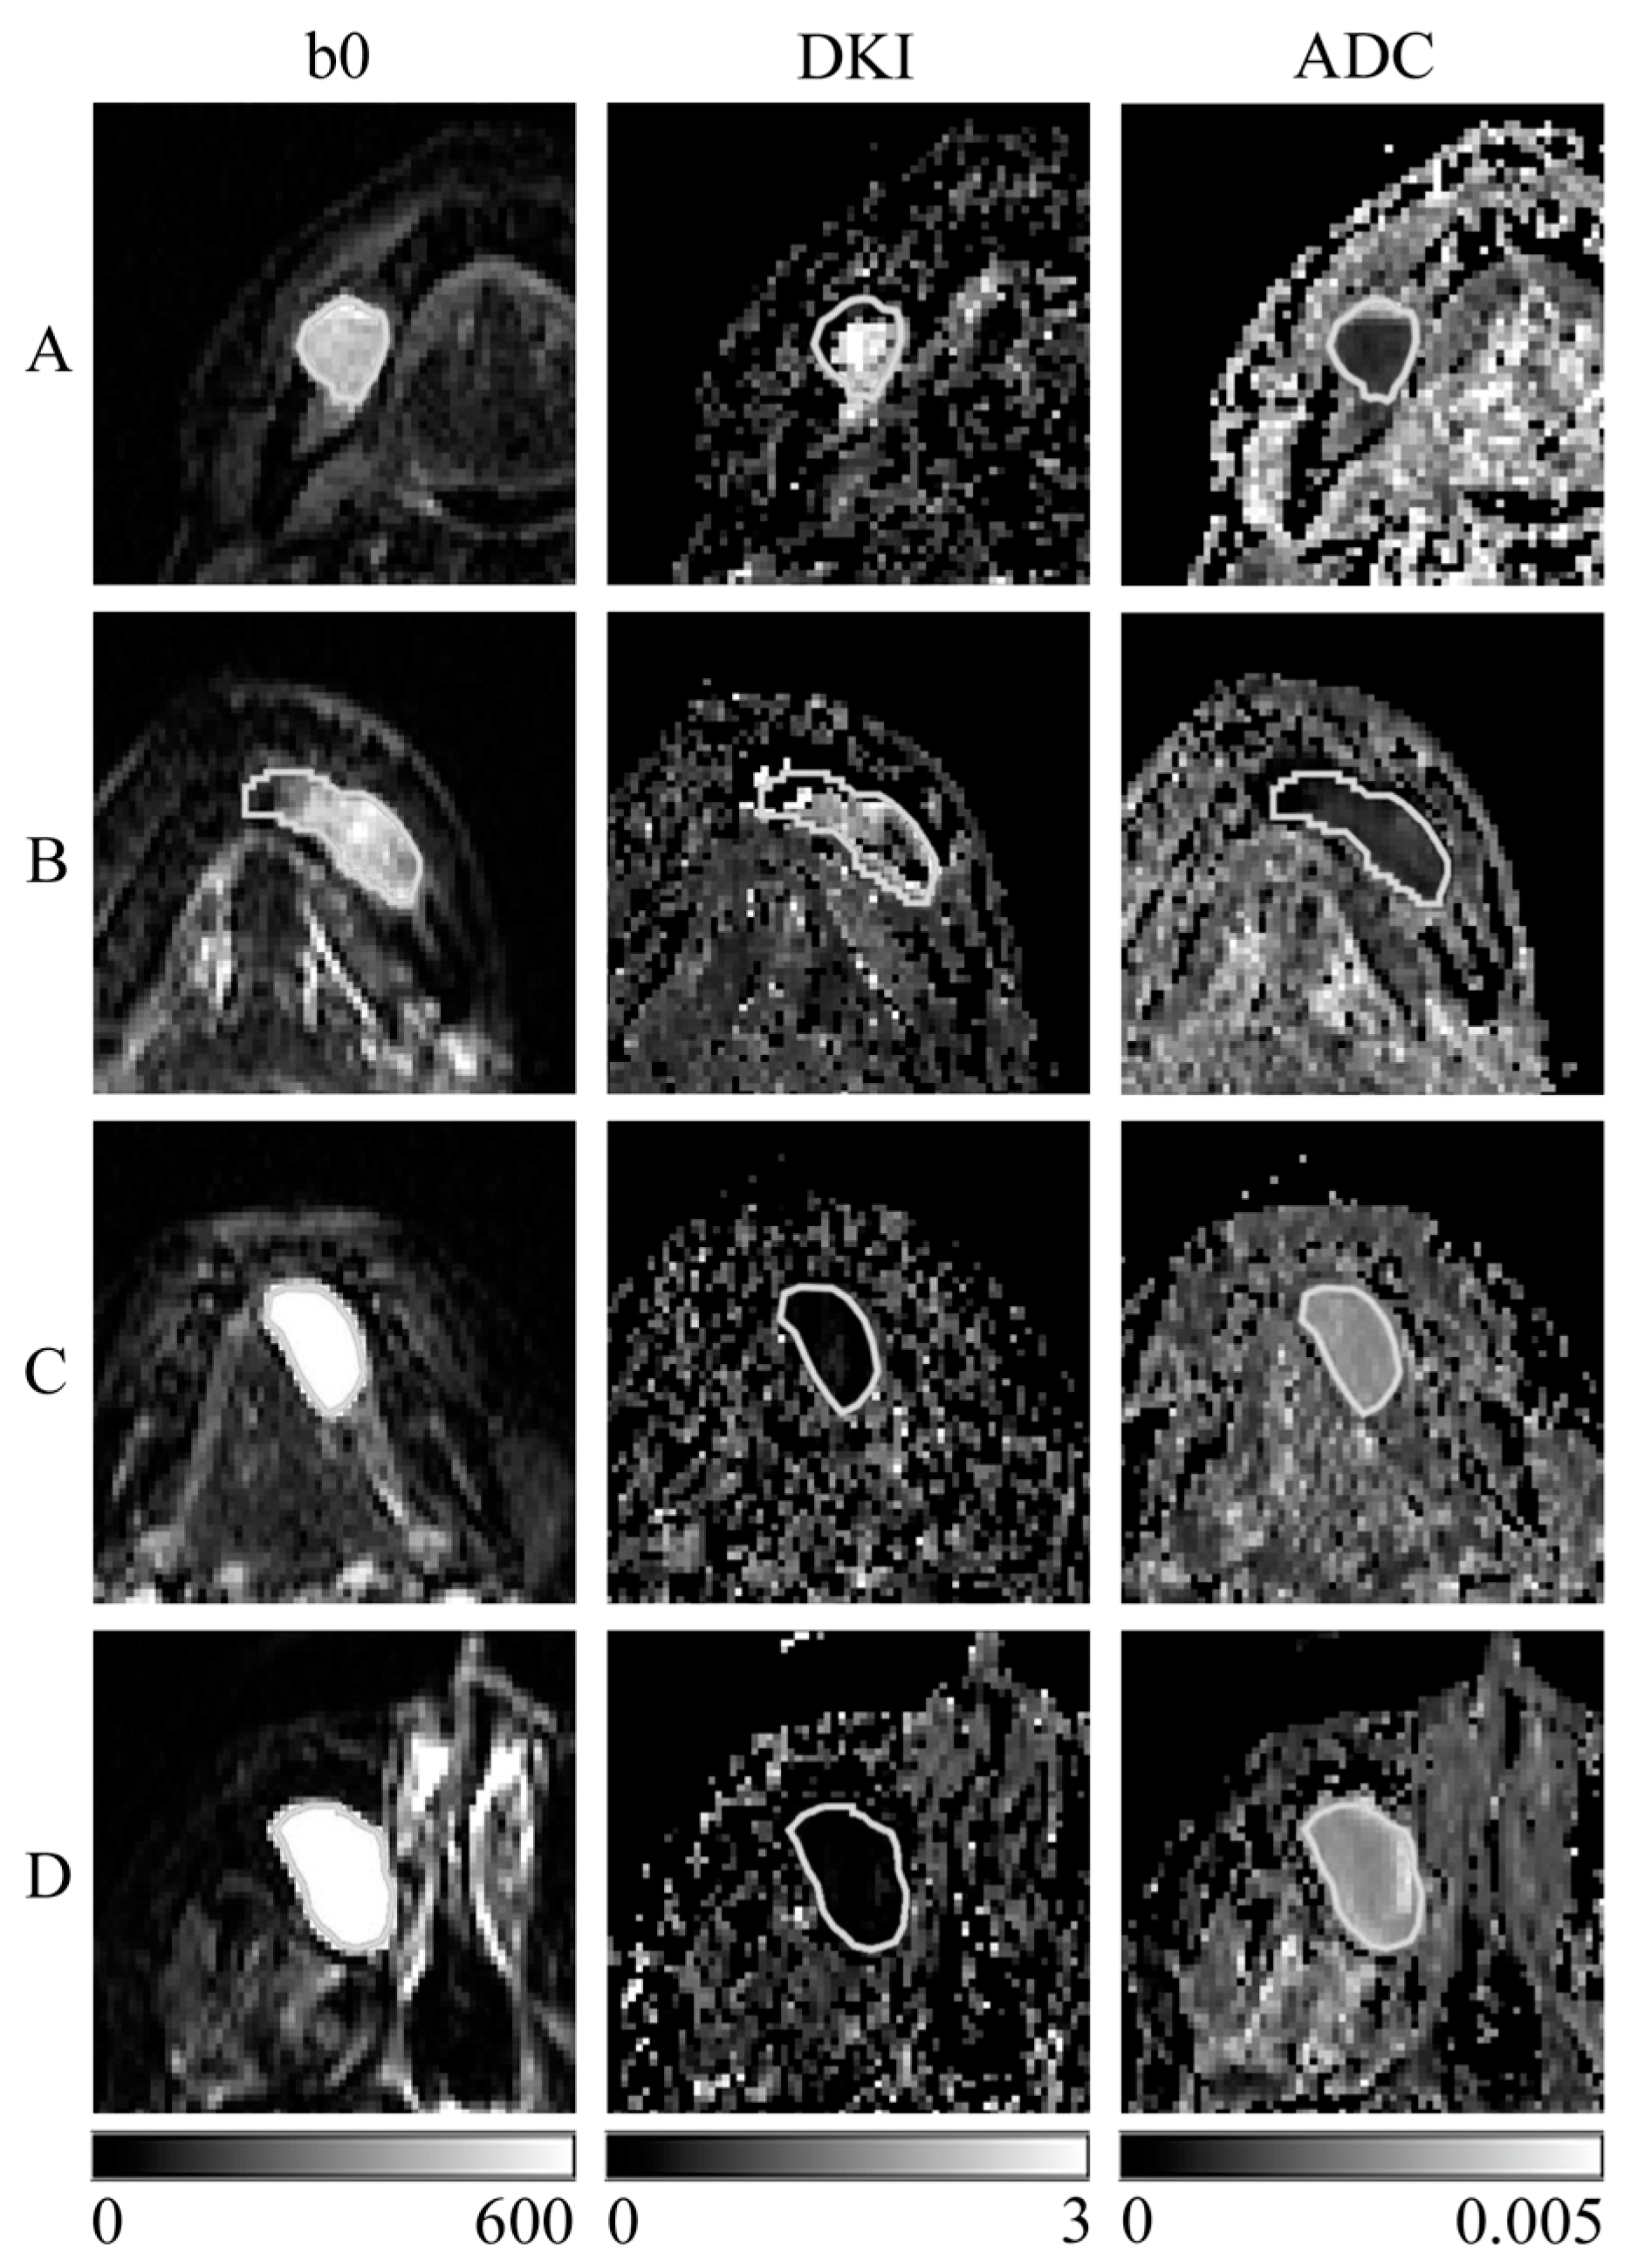

Figure 1 shows images of representative cases with an ROI. DC and OKC had lower signal values in DW images with a b-value of 0 s/mm2, higher MK values in DK images, and lower ADC values in ADC maps than R and M. The DK images of DC and OKC were more heterogeneous than the ADC maps.

Figure 1.

Representative images of each tissue sample are shown. (A) Dentigerous cyst; (B) odontogenic keratocyst; (C) ranula; (D) mucous cyst; (b0) diffusion-weighted (DW) images with a b-value of 0 s/mm2; (DKI) diffusion kurtosis (DK) imaging; and (ADC) apparent diffusion coefficient (ADC) map created with DK imaging using the same DW images with b-value 0, 400, and 800 s/mm2. The white line indicates cystic ROI. Scale bars indicate the displayed range of signal values for each image: DW image (0–600), DK imaging (0–3), and ADC map (0–0.005 mm2/s).

Because the DW image with a b-value of 0 s/mm2 is a T2-weighted image, the signal values of DC and OKC in the DW image with a b-value of 0 s/mm2 (Figure 1) were lower than those of other cysts, which, together with the reasons for the higher MK values in the DK image and lower ADC values in the ADC map, may be related to the characteristic components of the cyst.